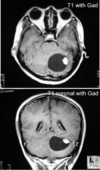

60 anos

Craniofaringioma Papilar Realce periférico e heterogêneo Calcificação não é comum Adultos

Craniofaringioma papilar Comum em adultos Calcificação é rara Componente cístico pode ocorrer mas não é um achado proeminente

200